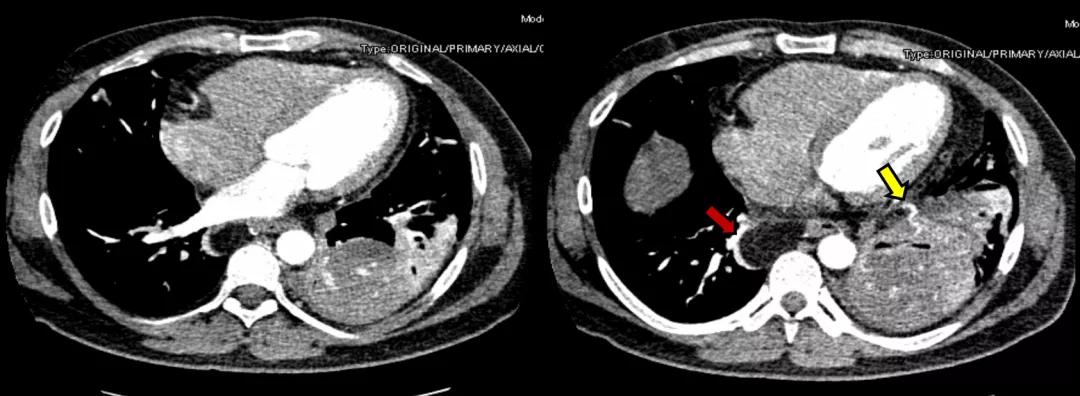

根据上述分析,下一步需要进行哪些检查呢?2020年5月8日,对该患者行胸部血管三维增强扫描:1、左肺下叶团片影区域见肺动静脉走行,肺动脉管腔内似见充盈缺损,考虑灌注不均。肺栓塞待排。左肺下叶团片影区域似见右膈下动脉分支走行,右膈下动脉增粗。2、心脏增大,肺动脉干稍增粗。3、左肺下叶后基底段见不规则团片影,较大层面约6.5×6.1cm,其内见少许点状钙化灶,增强后轻度强化,周围见斑片、条索影,邻近胸膜增厚、黏连。4、双肺多发小结节,多系炎性。5、双肺散在少许条片影及条索影,多系炎症。6、左侧少量胸腔积液。7、左肺门淋巴结稍大。8、食管裂孔疝,腹腔脂肪疝入。

图10:胸部血管三维增强扫描(2020-5-8)(黄色箭头:膈下来源的异常血管;红色箭头:食管裂孔疝)

双下肢静脉彩超:左侧股总静脉反流,未见深静脉血栓。

心脏彩超:左房稍增大,主动脉增宽,肺动脉稍增宽,室间隔增厚,左侧收缩功能测值正常。